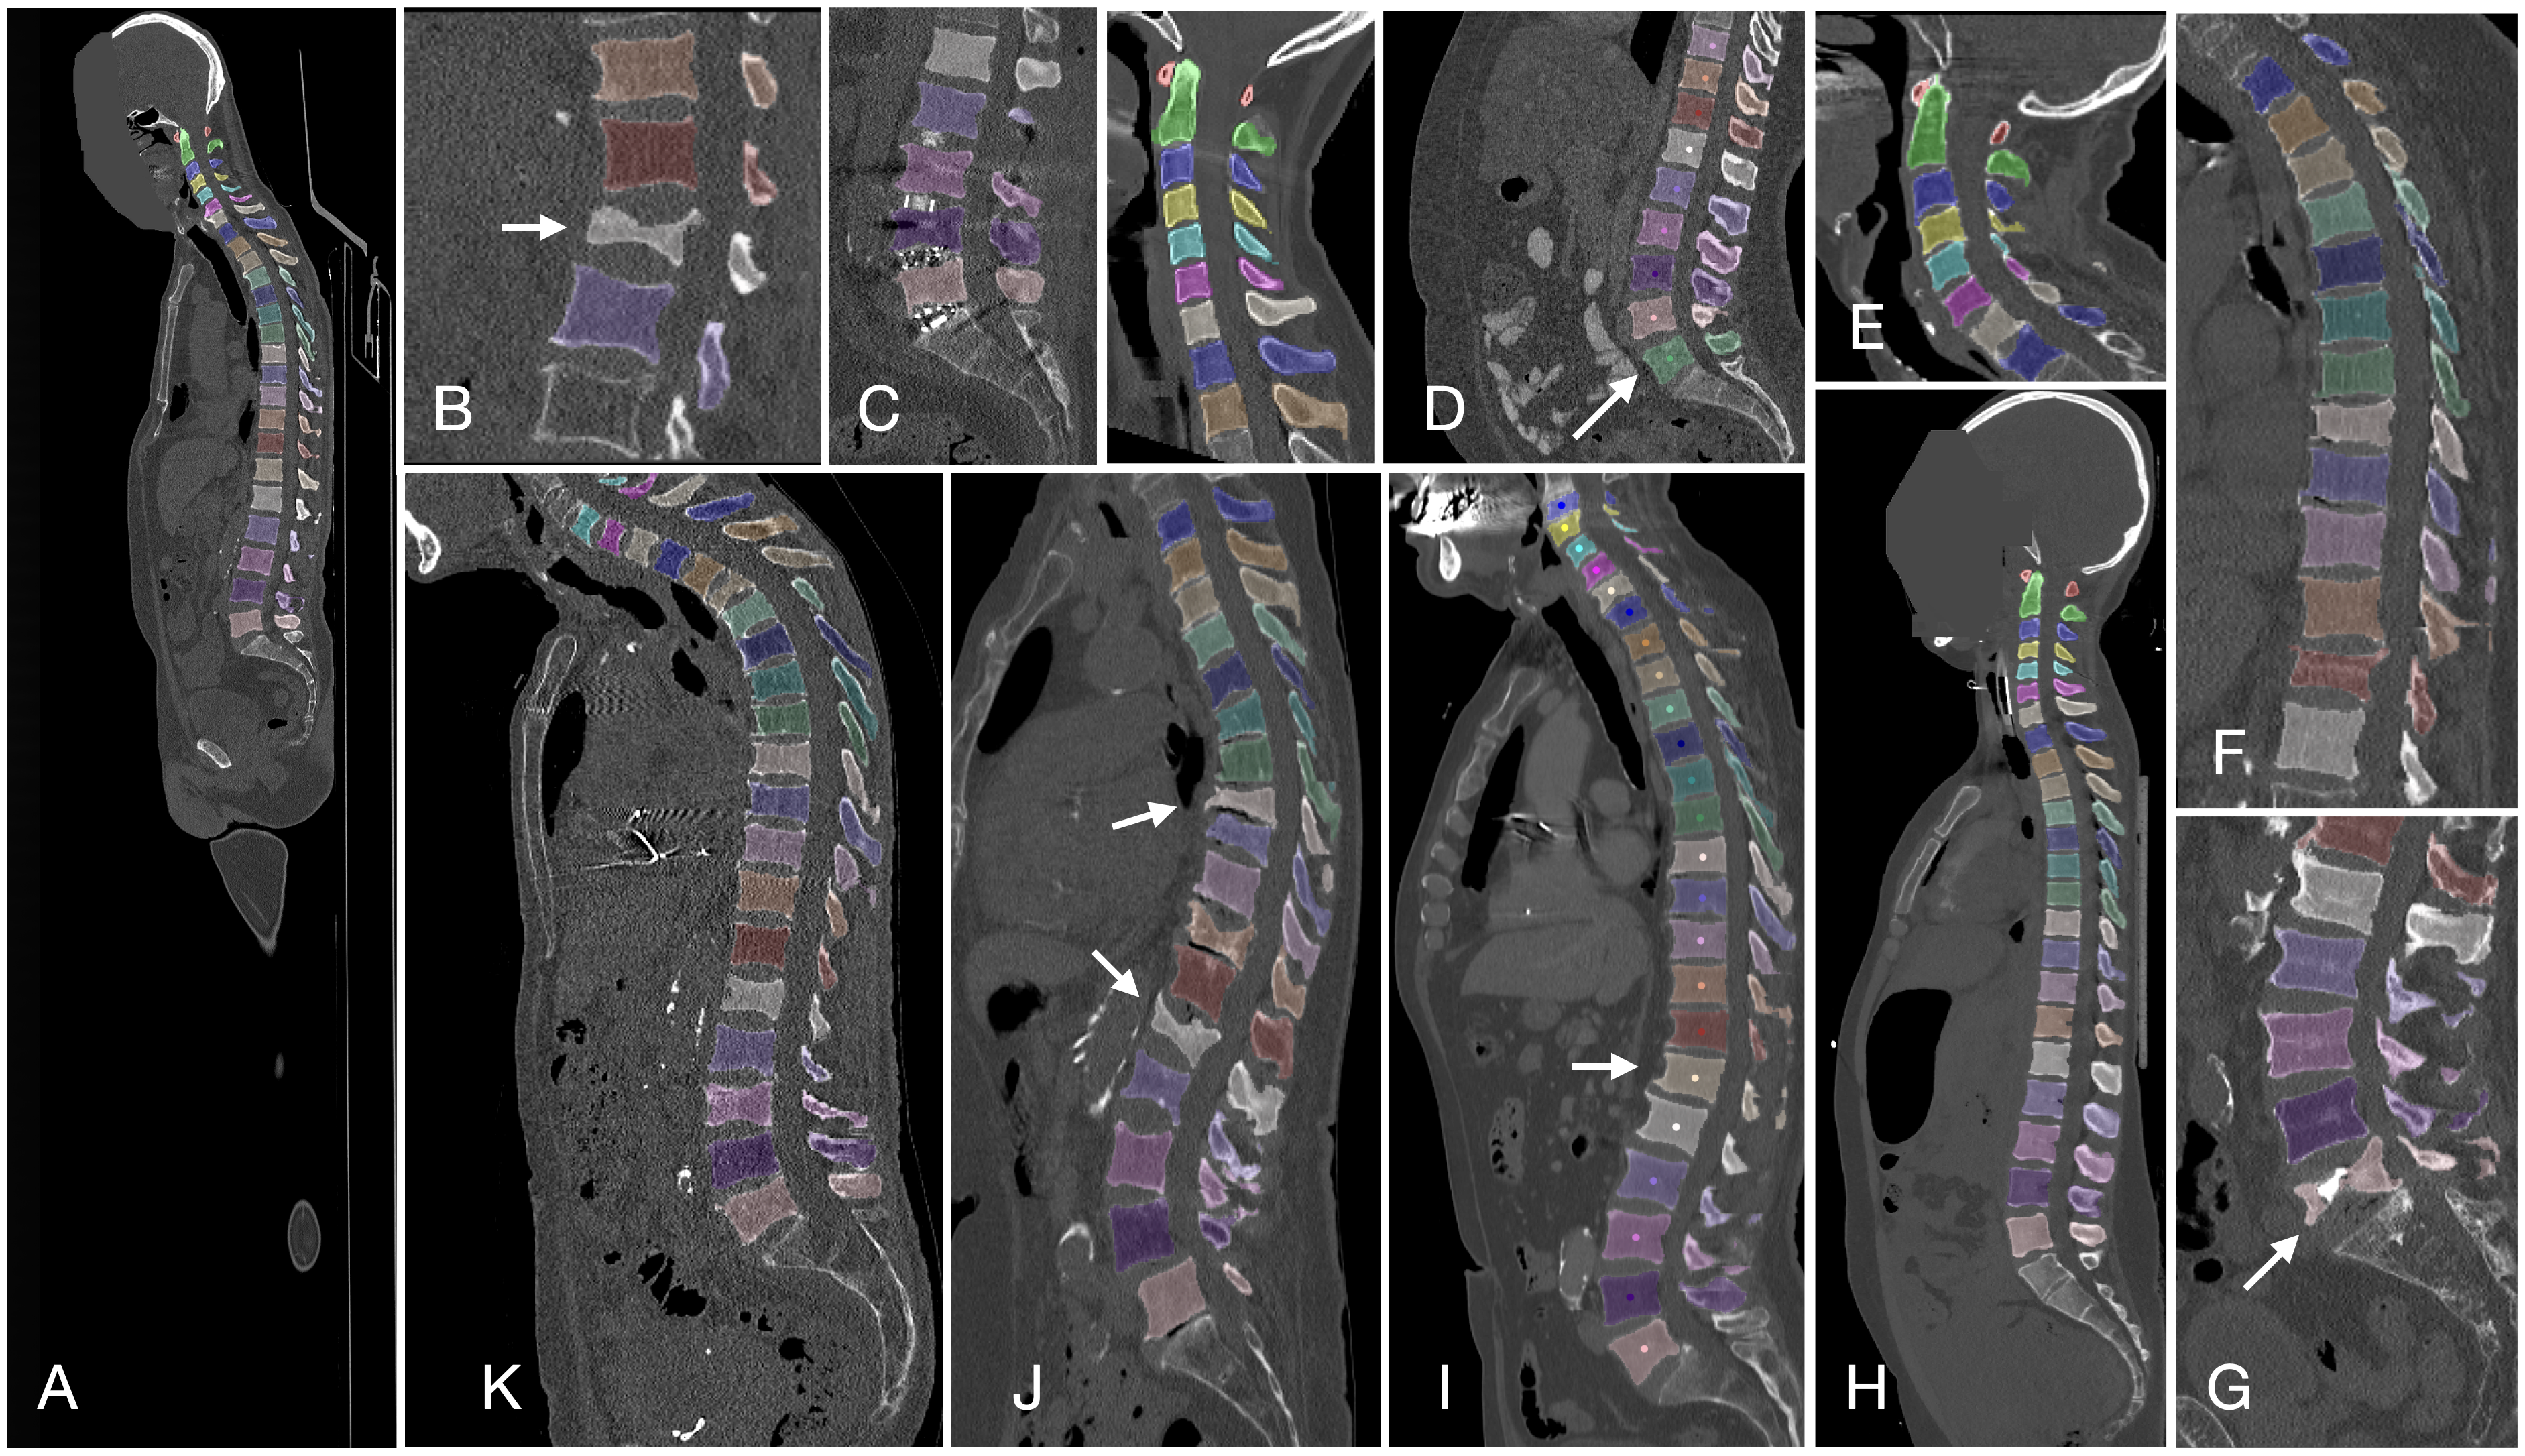

磁共振图像脊柱结构多类别三维自动分割

| 磁共振图像脊柱结构多类别三维自动分割 | 椎骨和椎间盘 | 分割 | MRI T2WI | 172 | 0/1 | nii | Custom |

脊椎

| VerSe | 脊椎 | 分割 | CC BY-SA 4.0 |